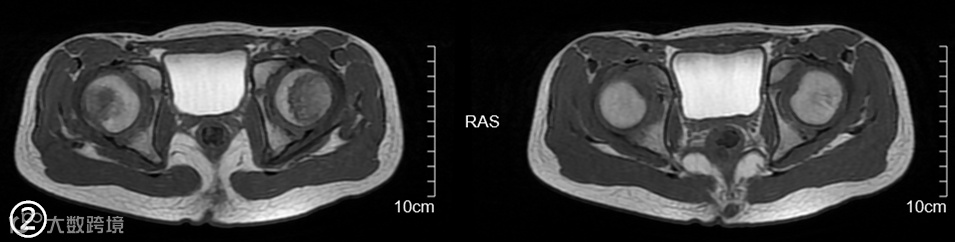

MRI图像上的组织信号与诸多因素相关,如序列、参数、组织本身的状态等。所以应首先要看是什么序列,使用的什么参数,目标组织的状态是怎样的。 -

MRI上的信号是相对的,没有绝对的高与低,而要看与谁比,在解读MRI图像信号时要选取信号相对稳定的组织作为参照对比,如肌腱,脑脊液。 -